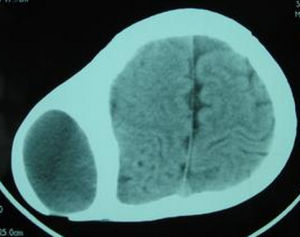

由小動脈或導血管破裂所引起。因帽狀腱膜下層組織疏鬆,血液易向各方向擴展,血液可充滿整個帽狀腱膜下層,使頭頂顯著增大,其含血量可達數百毫升。

可行常規物理檢查。2.CT檢查在頭部外傷時CT是最重要的影像學診斷方法,對新鮮出血敏感性高,並能顯示水腫及顱內壓增高繼發腦疝等重要病變。